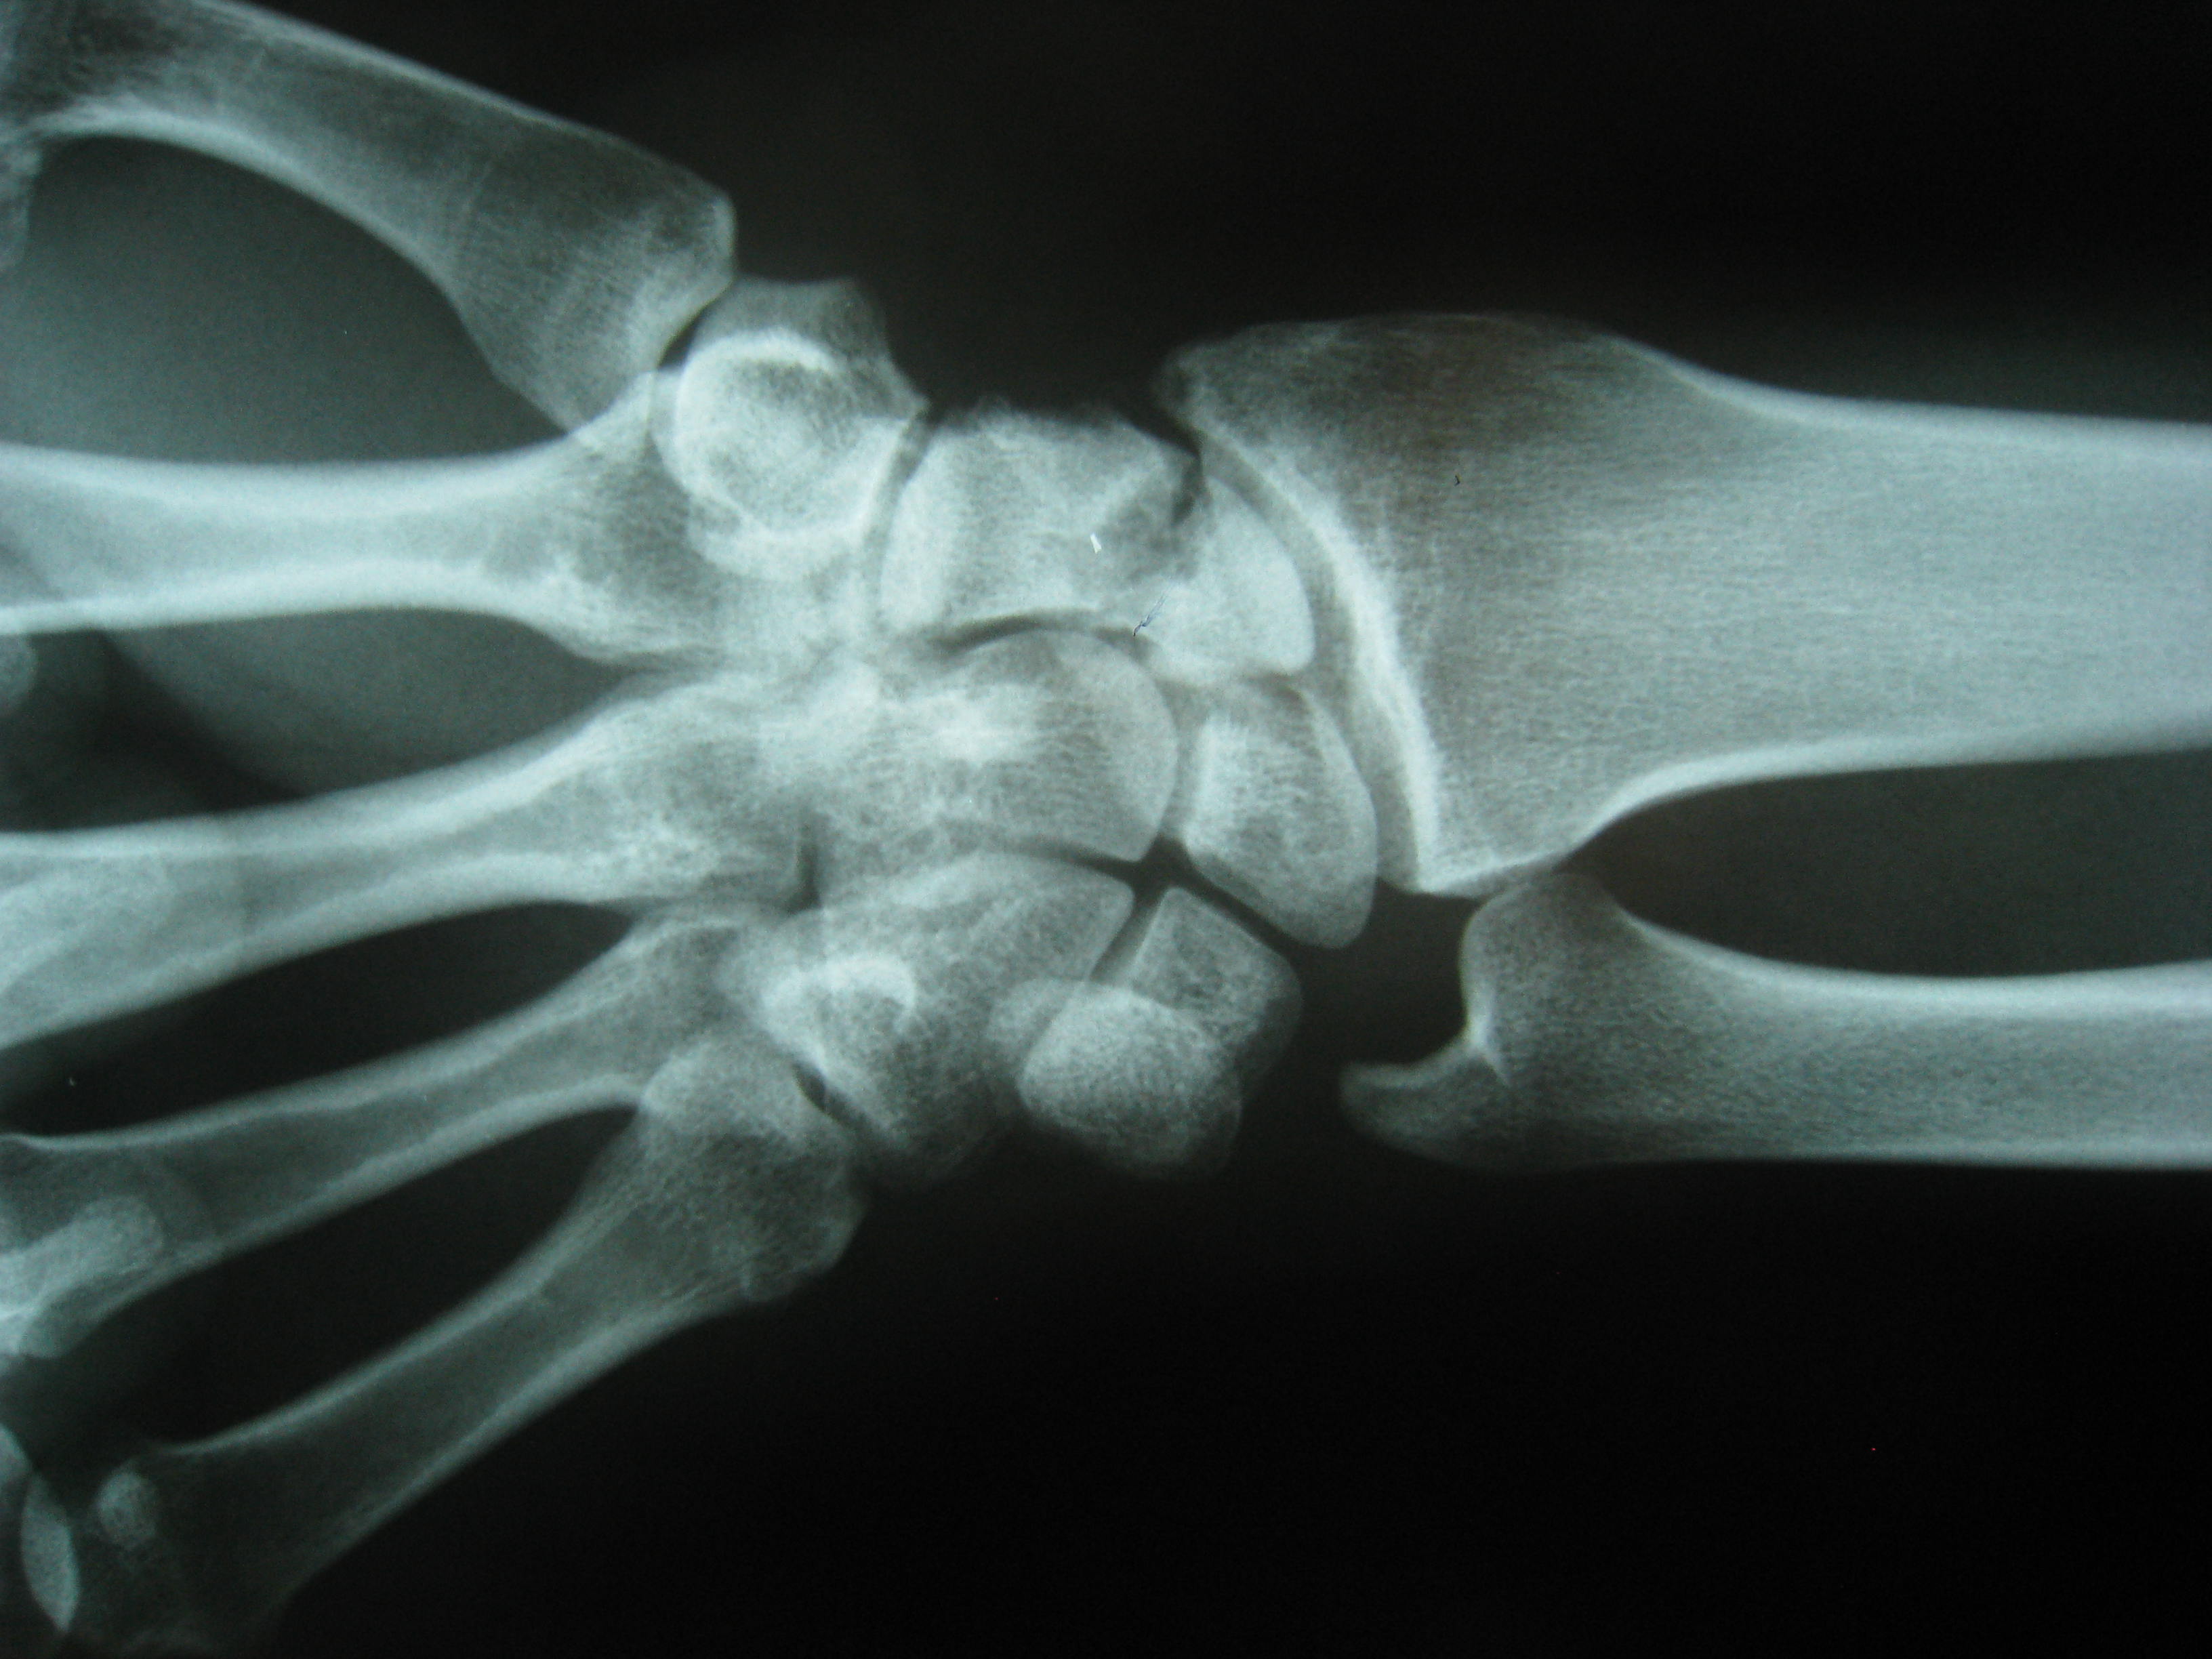

Ψευδάρθρωση σκαφοειδούς - Άσηπτη νέκρωση κεντρικού πόλου του σκαφοειδούς - Αγγειούμενα οστικά μοσχεύματα

Η ψευδάρθρωση καταγμάτων του σκαφοειδούς δεν είναι σπάνια επιπλοκή (βλ αντίστοιχο κεφάλαιο). Λόγω ανατομικών και φυσιολογικών ιδιαιτεροτήτων του σκαφοειδούς ή λόγω υποτίμησης των ενοχλημάτων εκ μέρους του αρρώστου, το κάταγμα συχνά διαφεύγει της αρχικής διαγνώσεως. Αυτό οδηγεί σε ανεπαρκή αντιμετώπιση, η οποία καταλήγει σε μη πώρωση (ψευδάρθρωση) του σκαφοειδούς. Η κατάσταση αυτή αρχικά έχει ελαφρά ή καθόλου συμπτώματα, με την πάροδο όμως των ετών εγκαθίσταται προοδευτικά επώδυνος περιορισμός της κινητικότητας του καρπού και ελάττωση της δύναμης δραγμού (αδύναμο σφίξιμο σε γροθιά).

Οσο κοντύτερα προς τον αγκώνα είναι το κάταγμα (κατάγματα του κεντρικού πόλου) τόσο μεγαλύτερη είναι η πιθανότητα να εμφανισθεί και νέκρωση του κεντρικού πόλου λόγω διακοπής της αιμάτωσης (άσηπτη νέκρωση). Αυτό καθιστά ακόμη πιο δύσκολη τον χειρισμό της ψευδάρθρωσης.

Προεγχειρητικά